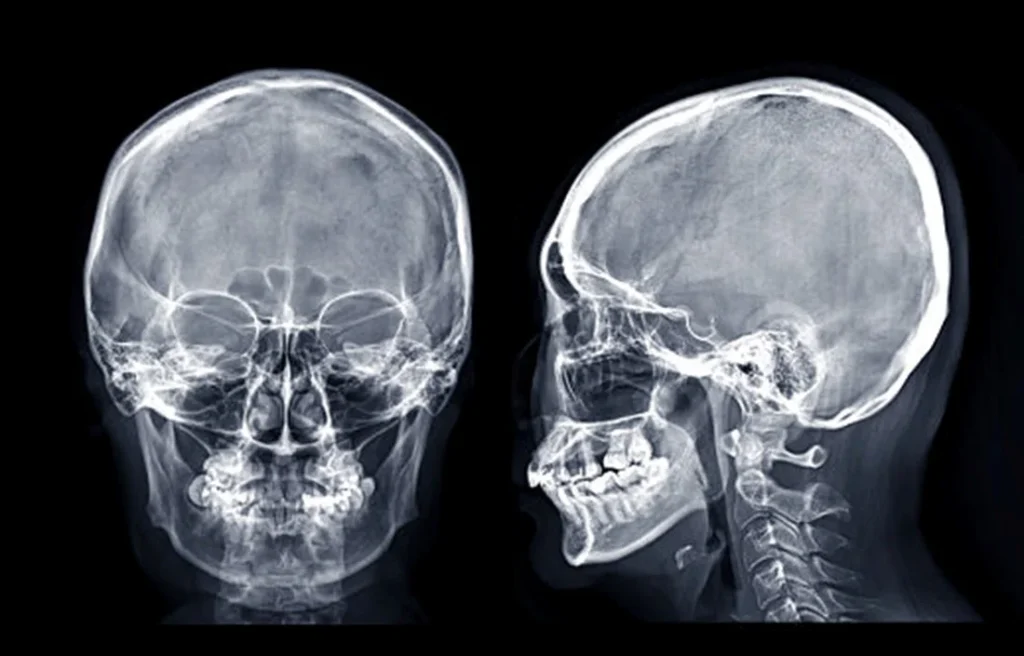

El procedimiento emplea una máquina de rayos X, compuesta por un generador que emite radiación en forma de un haz dirigido hacia el área de interés y una placa de imagen que capta la radiación tras su paso a través del cuerpo. Al atravesar el organismo, los rayos X interactúan de manera diferente con los tejidos. Por un lado, los huesos al ser más densos absorben más radiación y se ven blancos en la imagen, mientras que los tejidos blandos aparecen en tonos más oscuros.

La radiografía de columna total es una herramienta crucial que permite detectar diversas anomalías y condiciones que afectan a la columna vertebral. Dentro de estas se encuentran alteraciones congénitas, como escoliosis, artritis, lordosis y cifosis, así como alteraciones adquiridas y cambios degenerativos que pueden resultar de traumatismos, tales como tumores. A través de una visualización completa de la columna, es posible obtener un análisis detallado de cada una de estas deformidades, lo que resulta crucial para un diagnóstico preciso.

Además de estudiar directamente la estructura vertebral, esta radiografía permite evaluar el alineamiento de los ejes de carga en los miembros inferiores y observar posibles dismetrías pélvicas, asociadas tanto a la escoliosis como a diferencias en la longitud de las extremidades inferiores. De esta manera, el examen permite valorar el aspecto postural de la columna, lo que le entrega información valiosa sobre la postura general del paciente y cualquier desajuste que pueda estar presente.